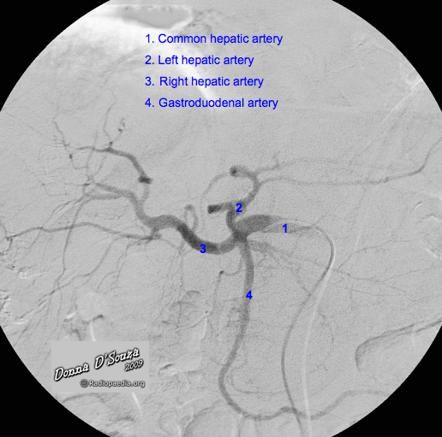

77.下圖中箭號所顯示為那一條血管出血?

(A)左胃動脈(left gastric artery)

(B)肝總動脈(common hepatic artery)

(C)右肝動脈(right hepatic artery)

(D)胃十二指腸動脈(gastroduedenal artery)